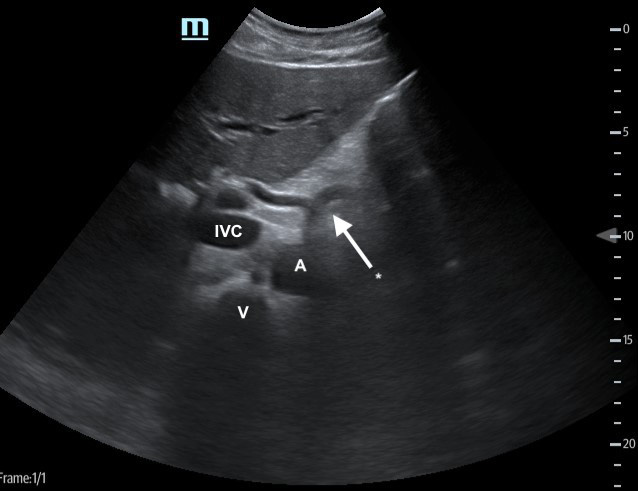

- Fan the transducer through the spleen to evaluate for focal splenic lesions.

- If no lesions are noted, switch to the high frequency linear transducer to evaluate the spleen for small focal hypoechoic lesions. (Video 5)

Figure 4. Spleen with low frequency (A) vs high frequency (B) transducers